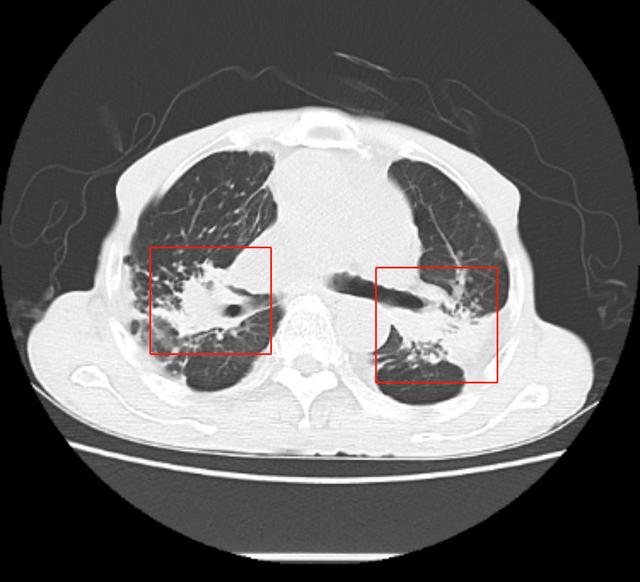

「是否需要进行肺移植手术,还是需要经过医生专业评估,结合患者自身身体状况,来最终决定的。」杨莉主任表示,经过入院胸部 CT 检查,可见陈大爷肺内多发由于粉尘沉积引起的肺部肿块,融合成团,如同白色水泥团块一样,紧紧地附着在患者两处肺门的地方,初步诊断矽肺。

陈大爷的 CT 报告